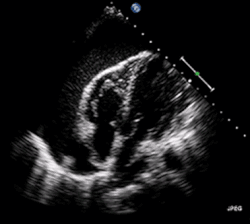

| A 2D echo transthoracic echocardiogram of pericardial effusion. The "swinging" heart. | |

ECG: may present with sinus tachycardia, low voltage QRS as well as electrical alternans.[2] Due to the fluid accumulation around the heart, the heart is further away from the chest leads, which leads to the low voltage QRS. Electrical alternans signifies the up-and-down change of the QRS amplitude with every beat due to the heart swinging in the fluid (as displayed in the ultrasound image in the introduction) .[1] These three findings together should raise suspicion for impending hemodynamic instability associated with cardiac tamponade.

Echocardiogram (ultrasound): when pericardial effusion is suspected, echocardiography usually confirms the diagnosis and allows assessment of the size, location and signs of hemodynamic instability.[4] A transthoracic echocardiogram (TTE) is usually sufficient to evaluate pericardial effusion and it may also help distinguish pericardial effusion from pleural effusion and MI. Most pericardial effusions appear as an anechoic area (black or without an echo) between the visceral and the parietal membrane.[1] Complex or malignant effusions are more heterogeneous in appearance, meaning they may have variations in echo on ultrasound.[5] TTE can also differentiate pericardial effusion based on the size. Although it's difficult to define size classifications because they vary with institutions, most commonly they are as follows: small <10, moderate 10–20, large >20.[5] An echocardiogram is urgently needed for evaluation when there is concern for hemodynamic compromise, a rapidly developing effusion or history of recent cardiac surgery/procedures.[1]